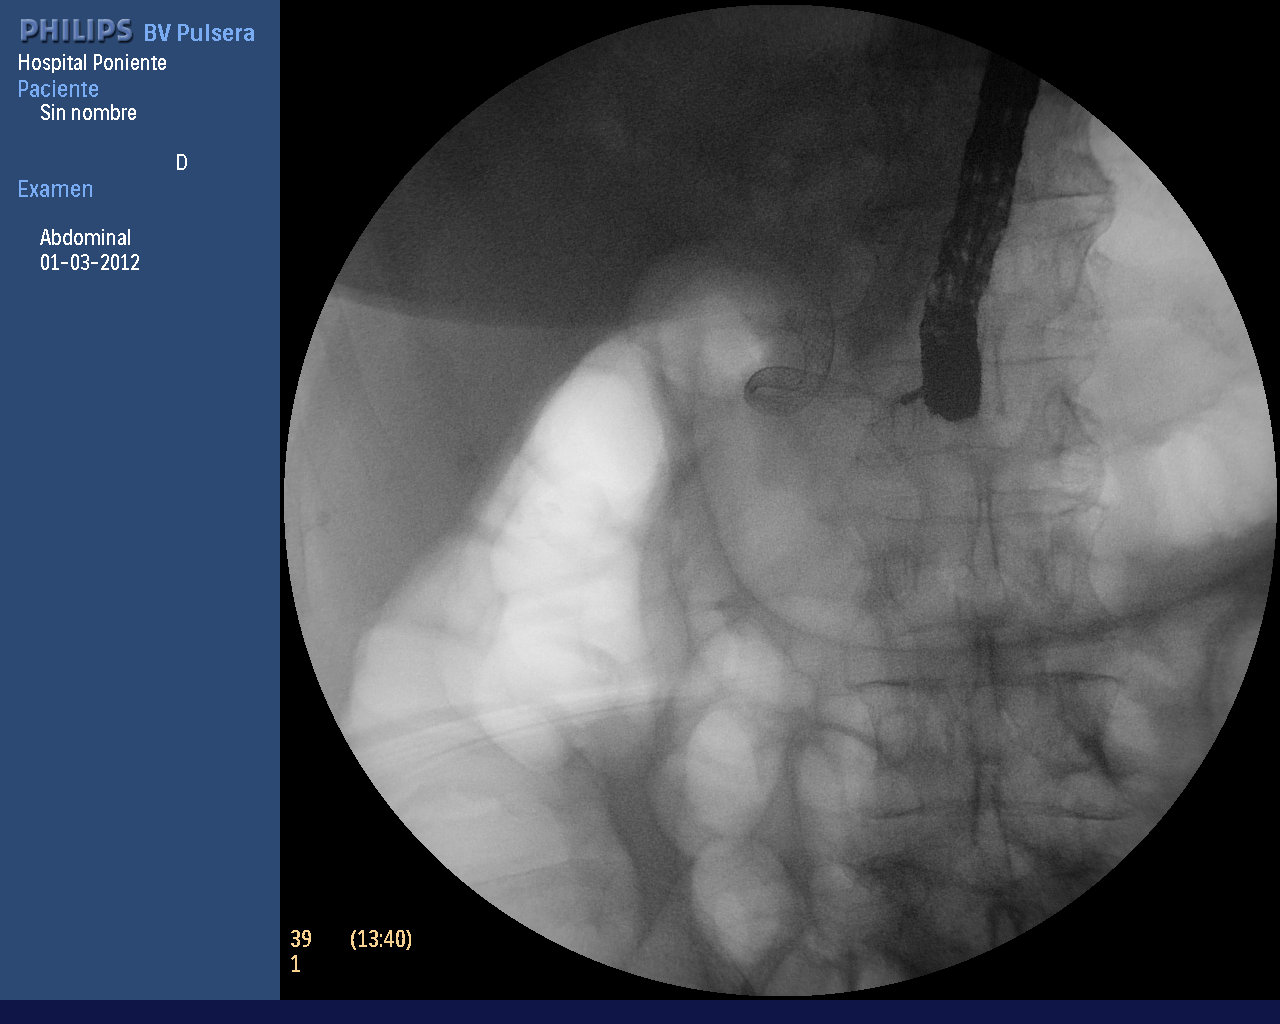

Paciente de 69 años con diagnóstico hace año y medio de estenosis subhiliar de dudoso origen (Bismuth I), colecistectomizada. En marzo de 2011 se realizó una colangioscopia (Spyglass) y se tomaron biopsias de una lesión que parecía tener un origen benigno (lesión papilomatosa biliar). Se decidió colocar una prótesis biliar completamente recubierta (Wallflex biliar de 6 cm de longitud) con excelente drenaje. Se recomendó a la paciente (según nuestro protocolo) un control de la permeabilidad y posición de la prótesis a los 6 meses, pero no acudió a la cita. Al año decide realizarse dicho control, pero se observa una migración interna de la prótesis con penetración de los hilos proximales en el borde inferior de la papila formando un anclaje sólido de ésta. La extracción con fórceps de dientes de ratón fue muy dificultosa, aunque finalmente se consiguió. Se colocó una nueva prótesis de las mismas características, pero dejándola algo mas sacada que en la CPRE anterior para evitar de nuevo la migración descrita. Por suerte, a pesar de la manipulación, la paciente no desarrolló ninguna complicación (perforación o PA) y fue dada de alta, con un control programado a los 6 meses.

Sin duda, las protesis biliares completamente recubiertas han supuesto un gran avance en el manejo de muchas patologías biliares. La facilidad de su extracción, incluso tras periodos largos de tiempo (> 6 meses) era una de sus grandes ventajas. Inicialmente se planteó usarlas en lesiones benignas (estenosis) con objeto de conseguir la dilatación mas rápida (6 meses) y con menos procedimientos que el tratamiento con múltiples prótesis plásticas. Con el tiempo, las indicaciones se extendieron al resto de patologías biliares (neoplasias, fugas biliares postquirúrgicas de gran débito, perforaciones postesfinteroplastia o tras papilotomía, etc). Nosotros las utilizamos en la mayor parte de las indicaciones, encontrando su mayor beneficio en las estenosis benignas. Hacemos un seguimiento a los 6 meses y si la prótesis sigue permeable y bien colocada se deja otros 6 meses mas, cambiándolas al año o retirándolas de forma definitiva si la estenosis se ha solventado. El único inconveniente que le hemos encontrado es que el riesgo de migración interna es algo mas elevado que las prótesis no recubiertas y en ocasiones, puede ser un problema para su recolocación-extracción. La hiperplasia granular reactiva que se produce el el área papilar puede llegar a ser muy importante y como en el caso descrito, penetrar en la mucosa haciendo muy dificil su extracción. Entre los métodos recomendados se encuentra el anclaje-tracción con balones de Fogarty de gran volumen (18 mm) así como la desimpactación de los alambres de la penetración mucosa con balones CRE y posterior extracción con forceps de dientes de ratón. Se aconseja que este tipo de prótesis se ajusten menos a la papila que las prótesis no recubiertas, dejándolas unos 5-6 mm hacia la luz duodenal.